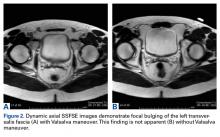

Imaging includes use of axial single-shot fast spin-echo with and without the Valsalva maneuver. Use of this maneuver increases sensitivity in detecting abdominal wall deficiencies, such as inguinal hernias (Figures 2A, 2B).

Figure 2.

Use of breath-hold axial single-shot fast spin-echo sequences with and without the Valsalva maneuver increased sensitivity in detecting pathologies—inguinal hernia and Gilmore groin in particular. On 24 of the 119 MRIs, the Valsalva maneuver either revealed the finding or made it significantly more apparent.

In our experience, the dynamic Valsalva sequence improves detection of true hernias and anterior abdominal wall deficiencies and should be included in each protocol for the evaluation of acute or chronic groin pain.